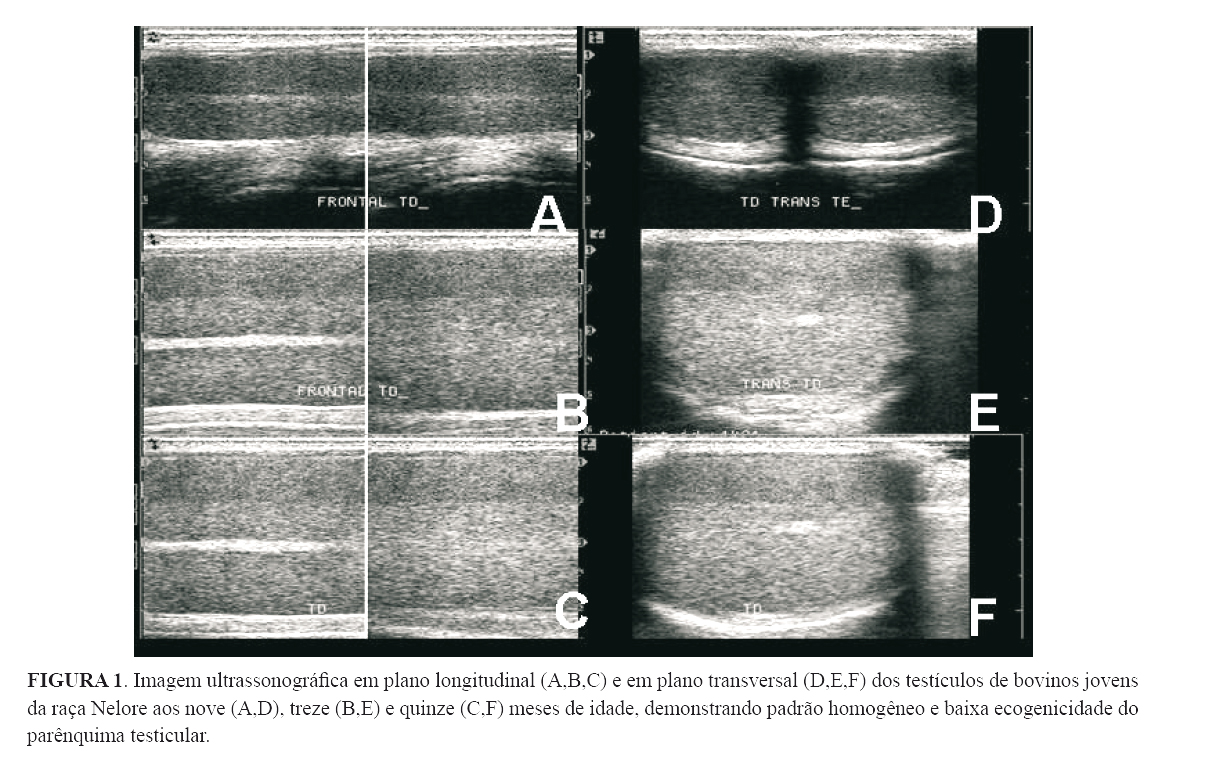

O parênquima testicular, nos três momentos da avaliação ultrassonográfica, mostrou-se homogêneo e com baixa ecogenicidade (Figura 1). Os valores médios das ecogenicidades testiculares aos nove, treze e quinze meses foram, respectivamente, 19,03%, 33,52% e 39,36%. Todos estes valores são diferentes (p<0,05). Assim, a ecogenicidade do parênquima testicular aumentou em proporção direta com a idade dos animais.

O mediastino testicular, em plano longitudinal, apresentou-se como uma linha hiperecoica no centro do parênquima testicular, com a espessura variando de 1,3 mm a 5 mm (Figura 2A). Em plano transversal foi visualizado como um ponto hiperecoico no centro do parênquima testicular (Figura 2B). Sua identificação tornou-se mais evidente com o avançar da idade, por se tornar a cada momento mais ecogênico.

O parênquima testicular de bovinos jovens da raça Nelore mostrou-se homogêneo e com baixa ecogenicidade até os quinze meses de idade. Este padrão de ecogenicidade reforça as afirmativas de que bovinos pré-púberes, mesmo sendo de raças diferentes da Nelore, apresentam baixa ecogenicidade testicular quando comparados com animais da mesma espécie, mas sexualmente maturos (PECHMAN & EILTS, 1987; CHANDOLIA et al. 1997; ARAVINDAKSHAN et al., 2000; BRITO et al., 2004; ABDEL-RAZEK & ALI, 2005).

Segundo CARDILLI et al. (2009), o parênquima testicular de bovinos jovens da raça Nelore é homogêneo e tem baixa ecogenicidade. Esta última aumenta em proporção direta com a idade dos animais, o que corrobora os resultados encontrados no presente estudo.